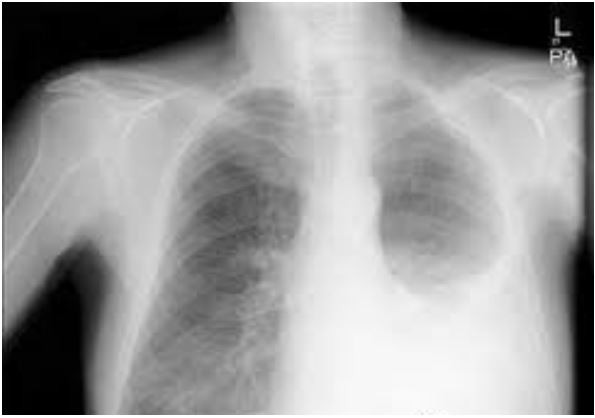

Menina, 8a, é trazida para atendimento por febre e tosse há 2 dias, com piora progressiva. Hoje com cansaço e falta de ar. Antecedente pessoal: asma em uso de beclometasona via inalatória 200 mcg 2x/dia. Exame físico: FR= 43 irpm, FC=120 bpm, T= 39ºC, pálido, retração intercostal e subcostal; oximetria de pulso (ar ambiente) = 90%; Pulmão: murmúrio vesicular diminuído em base esquerda, com estertores subcrepitantes à esquerda. Radiograma de tórax:

TRATA-SE DE UMA INSUFICIÊNCIA RESPIRATÓRIA: